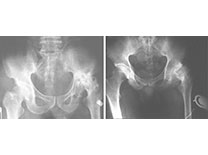

股骨头无菌性坏死

股骨头无菌性坏死是股骨头在无菌条件下发生的坏死。也叫股骨头缺血性坏死。坏死为骨结构破坏、骨组织营养中断、骨细胞死亡、骨小梁破坏等。外伤、饮酒、激素、放疗、动脉硬…【详细】